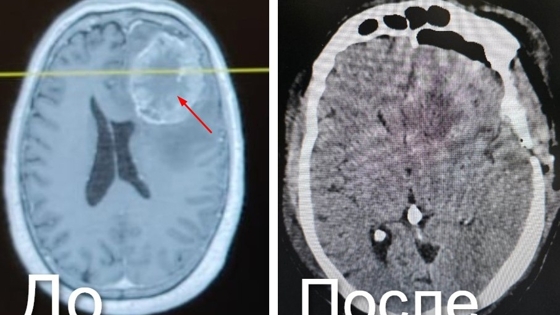

Как рассказал министр здравоохранения Кузбасса Андрей Тарасов, новообразование возникло как метастаз рака прямой кишки, перенесенного в 2019 году. Оказалось, что все эти годы кузбассовец не наблюдался у онкологов. В результате опухоль достигла размера 7,5х6 см, спровоцировала сильную боль, тошноту и потерю координации.

– Опухоль имела нечеткие границы и обильное кровоснабжение. Чтобы полностью удалить ее, специалисты использовали хирургический микроскоп и нейронавигационную систему, – рассказал Андрей Тарасов.